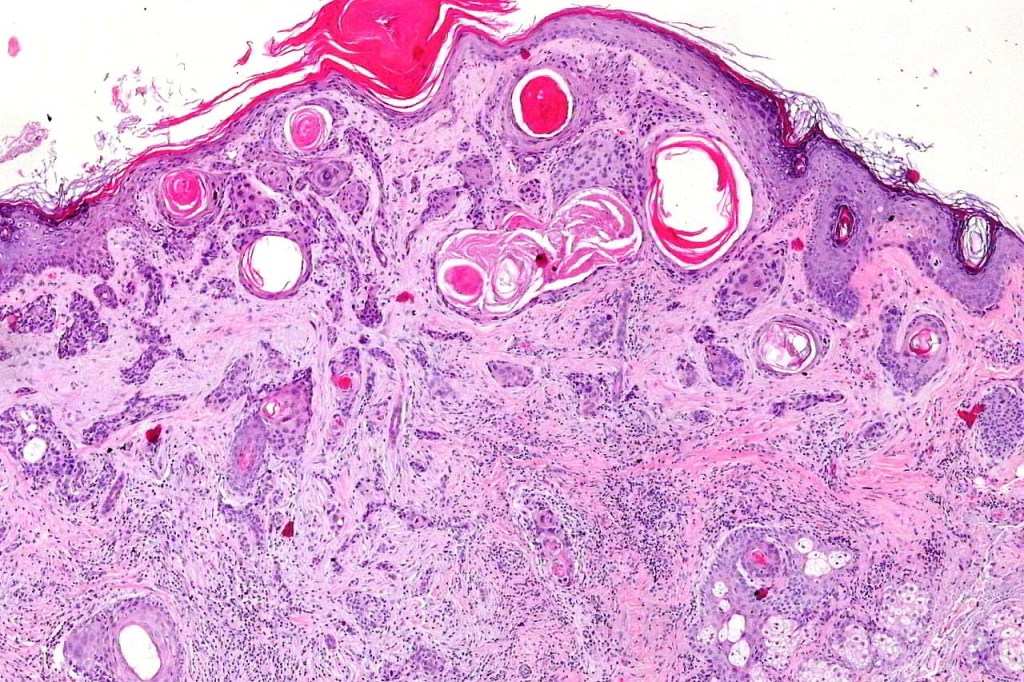

•Widely infiltrating biphasic tumor

•Superficial SCC

•Adenocarcinoma in deeper reaches

•Deep part may show both ducts and glands

•Microcystic adnexal carcinoma is sometimes confused with syringoid eccrine carcinoma. The former shows superficial keratocysts in the absence of SCC and in the deeper reaches, the epithelium is well differentiated & shows intracytoplasmic lumina and occasional well-formed ducts embedded in a dense fibrous stroma. Glands are not a feature